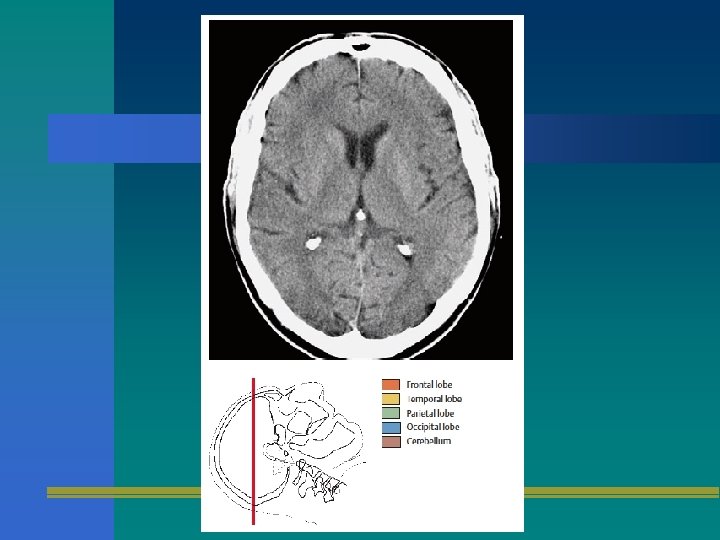

TOMOGRAFIA AXIAL

TAC